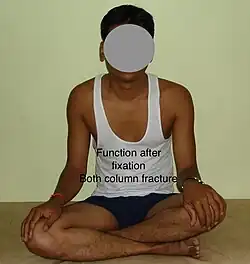

Function after fixation both column fracture

Function after fixation both column fracture

Function after fixation

Function after fixation

Depending on the stability achieved via initial treatment, the patient may be allowed to stand and walk with help of support within about six to eight weeks. Full function may return in about three months.